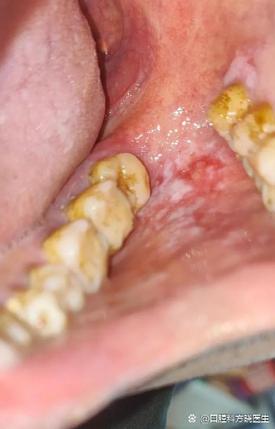

- 烫伤:这是最主要的原因,过热的食物或饮料(如热汤、热茶、火锅、刚出炉的面包)会直接烫伤口腔上颚娇嫩的黏膜,轻微烫伤会导致黏膜充血、水肿,然后坏死、脱落,形成白色或淡黄色的脱皮区域,并伴有疼痛感。

- 扁平苔藓:一种原因不明的慢性口腔黏膜炎症,表现为白色条纹或斑块,有时伴有糜烂和脱皮。

- 天疱疮:一种严重的自身免疫性疾病,口腔内会出现水疱,破溃后大面积脱皮,但这比较罕见。